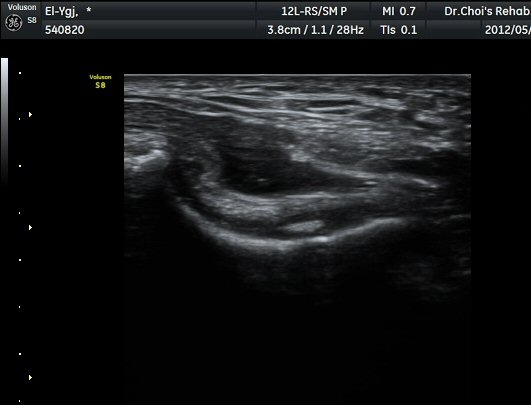

ÆÈ²ÞÄ¡ ³»Ãø Á¾´Ü¸é°ú Ⱦ´Ü¸é°Ë»ç¿¡¼­ ȰÂ÷ ¾Õ°ú °¥°í¸®µ¹±â¿Í(coronoid fossa)¿¡ ¼ö¾×Àú·ù°¡

°üÂûµÇ°í °¥°í¸®µ¹±â¿Í¿¡ °í¿¡ÄÚ »À µ¢¾î¸®°¡ °üÂûµÈ´Ù(±×¸² 2, 3).